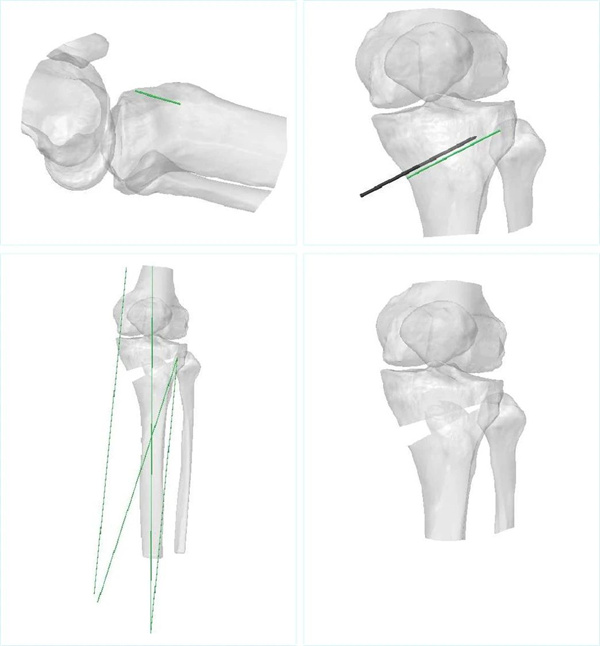

“AI骨科医生”术前精准模拟

AI手术规划软件根据患者的X光片和CT数据,经过算法分析,对患者骨骼解剖结构进行三维重建,生成精准的骨骼模型。

AI自动测量多项关键数据,完成畸形部位及角度判断、目标力线确定、合页和截骨线定位、截骨角度测算以及钢板放置位置推算等工作,最终形成可视化术前规划报告。

术前AI手术规划图

李兵表示,根据术者确认的手术目标,结合患者骨骼解剖结构,AI自动化解析并生成导板数据,进行3D打印。该导板具有与患者骨骼唯一匹配性,能够辅助术者在术中精准、稳定完成截骨操作。

3D打印PSI导板模型